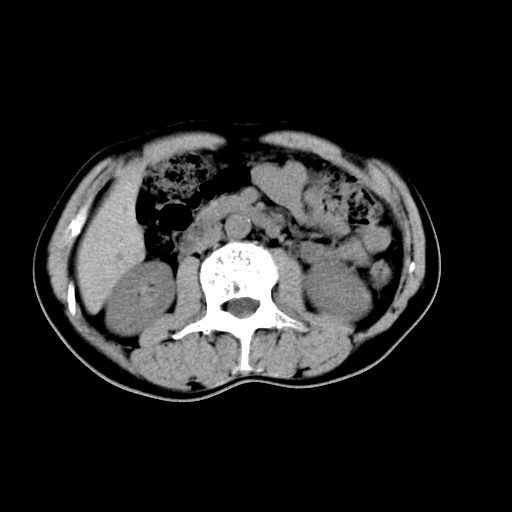

男,47岁,左输尿管结石碎石治疗后10余日。彩超示:左输尿管下段狭窄、输尿管积水。请各位讨论一下左输尿管下段结石还是静脉石?

象是第二狭窄处结石伴以上输尿管、肾盂轻度积水。

输尿管结石伴以上输尿管、肾盂轻度积水。

两侧髂总动脉壁斑状及点状钙化.左侧输尿管行经与左髂总动脉相交后见高密度影,且下段输尿管管腔未见扩张,应该要考虑结石伴以上输尿管及肾盂积水.但右侧结节状高密度影,也应该是结石吧!那以上输尿管未见扩张呢!因此静脉结石可能性也较大.请问楼主碎石前左侧输尿管结石位置.

虽左侧有轻度肾盂积水但不支持结石。1结石边周应该有软组织包绕呈晕征。2钙化点前面见输尿管影也不支持是结石。3彩超没提结石。建议超生复查。

输尿管先位于腹部,后进入盆腔,最后斜穿膀胱壁开口于膀胱,因此,临床上常将输尿管分为腹段、盆段和壁内段。第1个狭窄:在肾盂与输尿管移行处。第2个狭窄:在跨过髂血管处。第3个狭窄:在穿过膀胱壁处。这些狭窄是结石容易滞留的部位。

左侧输尿管有轻度扩张伴有肾盂积水,输尿管下段周围的高密度影不象在输尿管内。

同意,不支持结石。(因显示该高密度影前见扩张输尿管影,另外两侧对称显示)。

左侧高密度影在左侧输尿管的内侧方,所以不考虑输尿管结石.

我认为不是结石的可能性大,因为他的位置和血管钙化的位置邻近